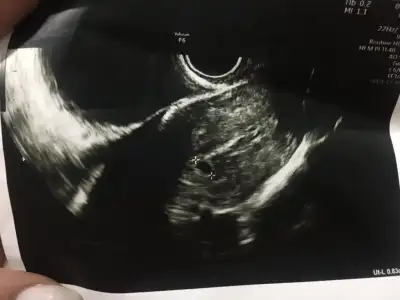

kesenin içi boş görünüyor 8mm haftasına göre boyutu da küçük sanırım ama doktora sorduğumda küçük demedi 1 hafta içindeki gelişimi önemli dedi belki de stres yaptırmamak için öyle dedi bilmiyorum. 5+2 den bu ultrason

kese gayet saglıklı görunuyor ama